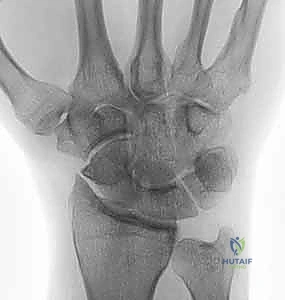

- التصوير بالأشعة السينية (X-rays): هي الخطوة الأولى والأساسية. تظهر الأشعة بوضوح تآكل الغضروف، تضيق المسافة المفصلية، وتكوّن الزوائد العظمية (المنقار العظمي).

- التصوير بالرنين المغناطيسي (MRI) أو الأشعة المقطعية (CT Scan): في الحالات المعقدة، أو لتقييم حالة الأربطة والعظام المجاورة بشكل ثلاثي الأبعاد، يعتمد الدكتور هطيف على هذه التقنيات المتقدمة لضمان تخطيط جراحي لا تشوبه شائبة.

| الأشعة السينية | مسافة مفصلية واضحة، عظام ناعمة | تضيق المسافة المفصلية، تكون نتوءات عظمية (Osteophytes)، وتصلب العظم تحت الغضروف |